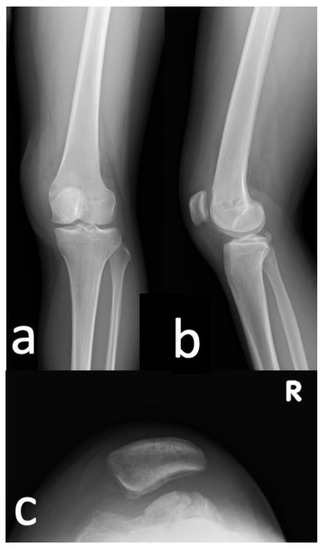

2.1. Case